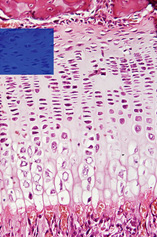

The blue rectangle in the upper figure indicates the region that is detailed in the lower figure.

Observe in the lower figure:

1 – Zone of resting cartilage.

This Zone is adjacent to the bone of the epiphysis.

The bone is the reddish band in the uppermost region of the figure that does not become highlighted when using the mouse or clicking on the image. It can be recognized by the presence of osteocytes placed in a red/pink extracellular matrix (ECM).

The resting cartilage, on the other hand, has the typical morphology of a hyaline cartilage – it is formed by chondrocytes (highlighted in red after using the mouse or clicking) surrounded by a bluish ECM (highlighted in a dark tone of blue).

2 – Zone of serial cartilage. The chondrocytes of this zone (highlighted in red) divide actively by mitosis and become organized in rows, like stacks of coins. The cartilaginous matrix is highlighted in light tone of blue.